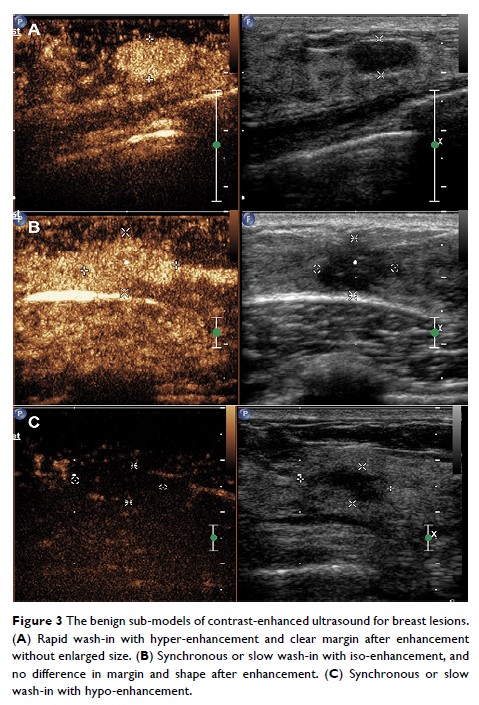

- 作者:Jiabin Zhan, Shuai Zhang, Xin Wei, Yihui Fu, Jing Zheng

- 期刊:Cancer Management and Research